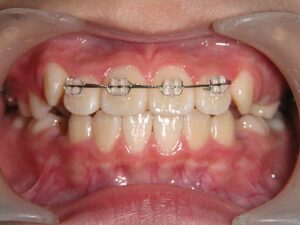

第2期治療終了時

口腔内写真

治療結果

上下の歯のデコボコが改善

全体的な咬み合わせの緊密化

患者様は歯のデコボコを主訴で来院しましたが、第1期治療で歯列拡大+前歯部矯正を行ったことで、第2期治療で非抜歯矯正にて治療終了することができました。

第1期治療で上記のアプローチをせず、第2期治療から開始していた場合、抜歯矯正になっていた可能性が高い患者様でした。